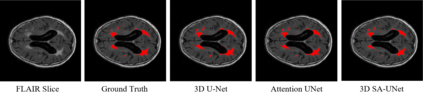

White Matter Hyperintensity (WMH) is an imaging feature related to various diseases such as dementia and stroke. Accurately segmenting WMH using computer technology is crucial for early disease diagnosis. However, this task remains challenging due to the small lesions with low contrast and high discontinuity in the images, which contain limited contextual and spatial information. To address this challenge, we propose a deep learning model called 3D Spatial Attention U-Net (3D SA-UNet) for automatic WMH segmentation using only Fluid Attenuation Inversion Recovery (FLAIR) scans. The 3D SA-UNet introduces a 3D Spatial Attention Module that highlights important lesion features, such as WMH, while suppressing unimportant regions. Additionally, to capture features at different scales, we extend the Atrous Spatial Pyramid Pooling (ASPP) module to a 3D version, enhancing the segmentation performance of the network. We evaluate our method on publicly available dataset and demonstrate the effectiveness of 3D spatial attention module and 3D ASPP in WMH segmentation. Through experimental results, it has been demonstrated that our proposed 3D SA-UNet model achieves higher accuracy compared to other state-of-the-art 3D convolutional neural networks.